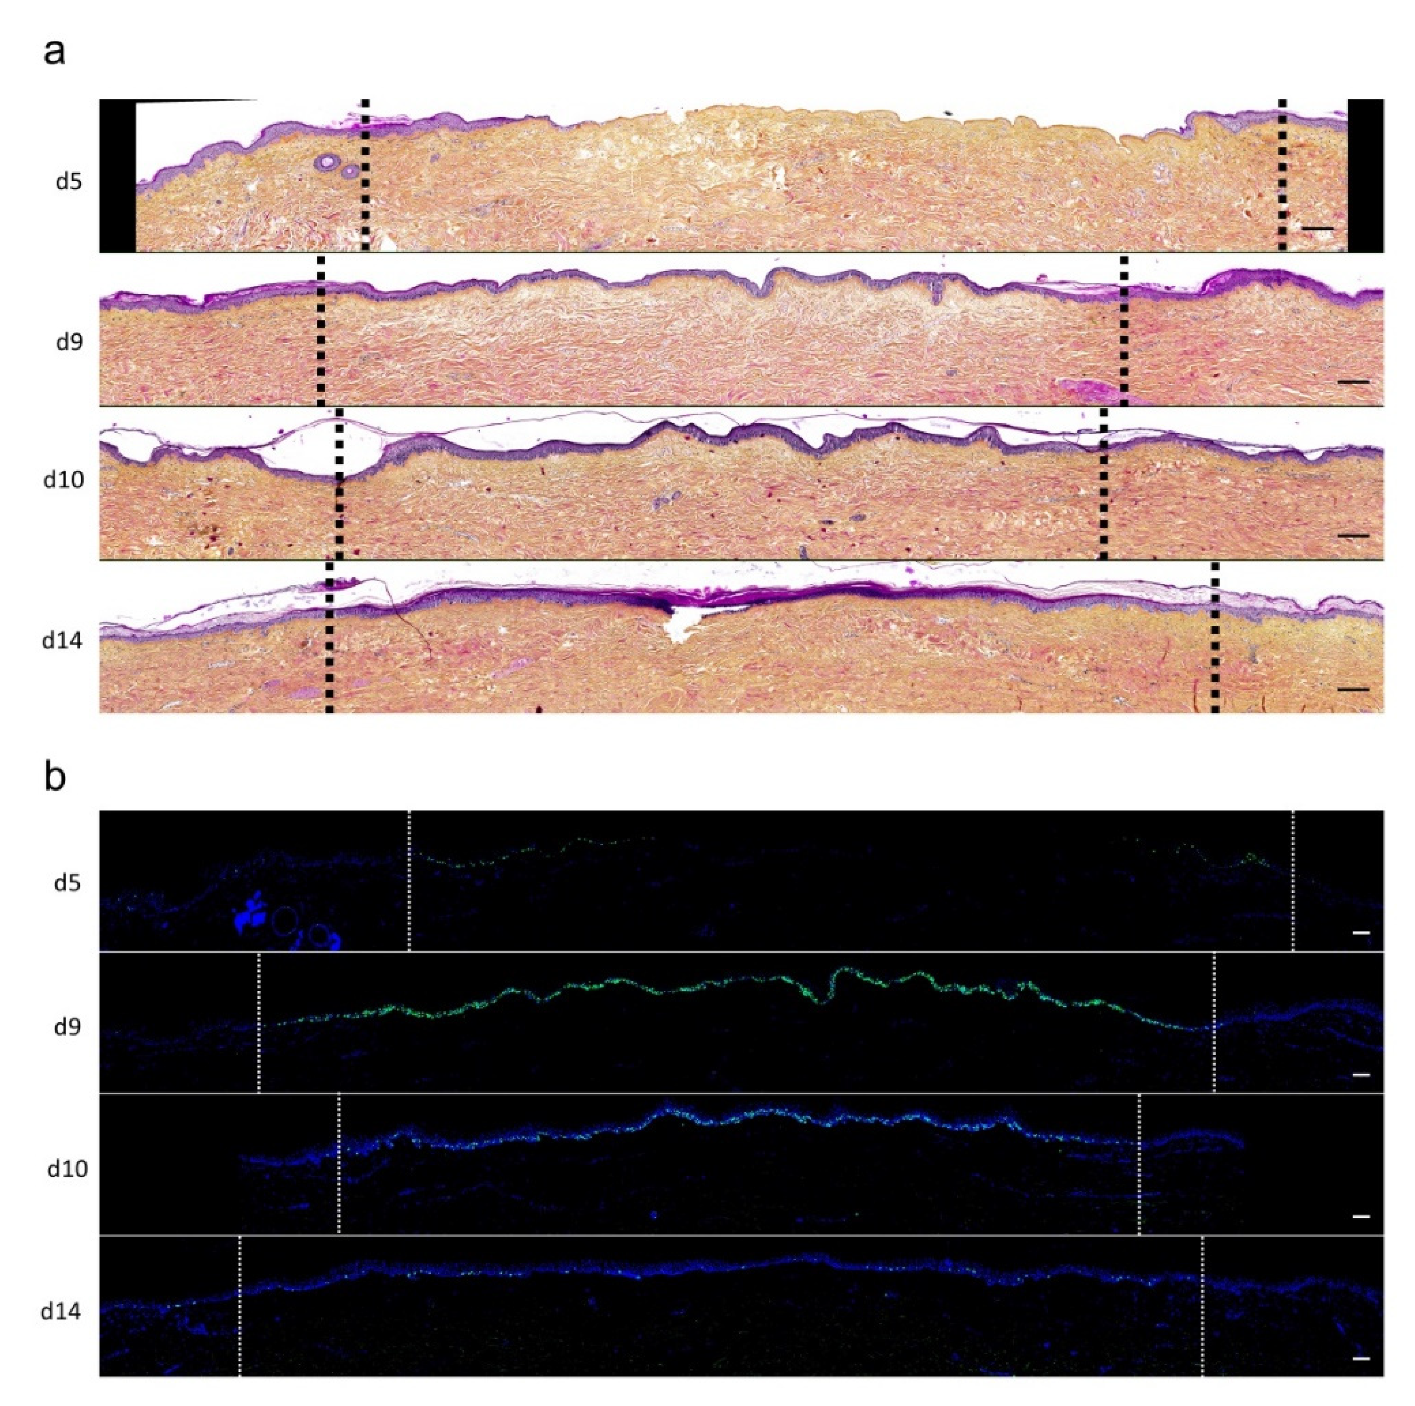

2.3. Kinetics of Re-Epithelialization in Human Skin Explants Subjected to Experimental Deep-Second Degree Burn Injury